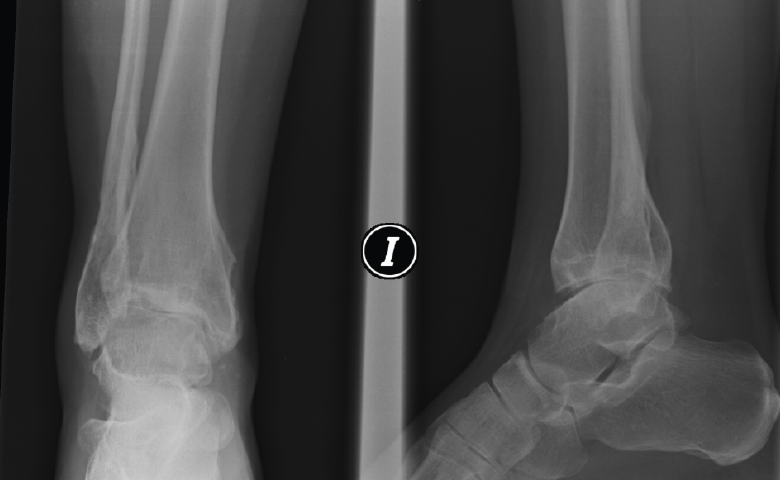

Figura 6. Artrosis postraumática de tobillo tras fractura bimaleolar hace 15 años.

Figura 7. Caso de la Figura 6 con distracción articulada.

Figura 8. Caso de la Figura 6 a los 3 años de la distracción articulada. Obsérvese el mantenimiento del espacio articular a nivel de la articulación del tobillo.